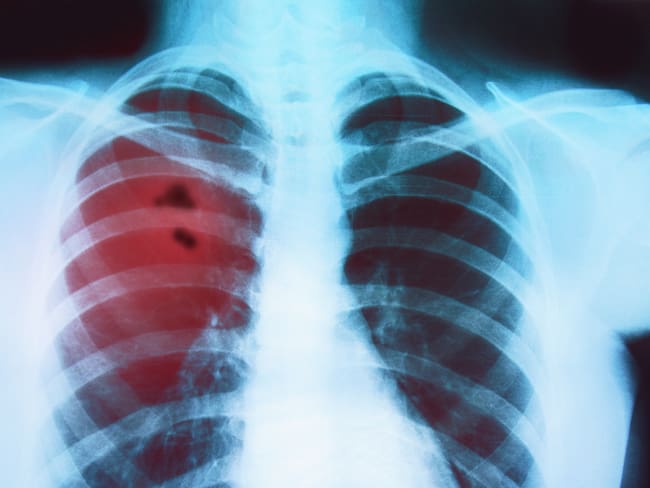

Cáncer de Pulmón. Foto: Getty Images / Fetrinka